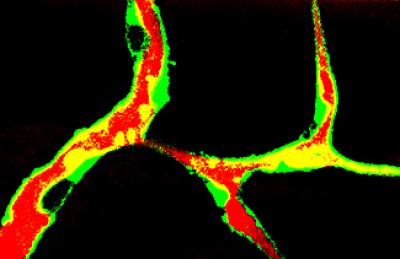

Cholesterol sets off chaotic blood vessel growth

A study at the University of California, San Diego School of Medicine identified a protein that is responsible for regulating blood vessel growth by mediating the efficient removal of cholesterol from the cells. Unregulated development of blood vessels can feed the growth of tumors.

Cholesterol is a structural component of the cell and is indispensable for normal cellular function, although its excess often leads to abnormal proliferation, migration, inflammatory responses or cell death. The researchers studied how the removal of cholesterol from endothelial cells (cells that line the blood vessels) impacts the development of new blood vessels, the process called angiogenesis.

"Too much cholesterol increases the abundance of lipid rafts, areas in the plasma membrane where surface receptors initiate signaling events leading to angiogenesis," Miller said. VEGFR2 is such a receptor, playing a central role in the development of blood vessels. Research into the process of angiogenesis suggests that VEGF-induced signaling within endothelial cells is important to tumor growth.

In this study, the scientists show that apoA-I binding protein (AIBP) is secreted by surrounding tissues and facilitates cholesterol removal from endothelial cells. This process interferes with the VEGFR2 receptor function, in turn inhibiting angiogenesis.

"Studying the process in zebrafish, we found that the timing and the pattern of AIBP expression is such that it helps guide segmental arteries to grow strictly in the dorsal direction, instead of an aberrant sideways direction," said first author Longhou Fang, who added that future studies will explore if AIBP or its derivatives can be used to inhibit pathologic angiogenesis in tumors. Alternatively, blocking AIBP activity in the heart may, in principle, stimulate re-growth of blood vessels after a heart attack.